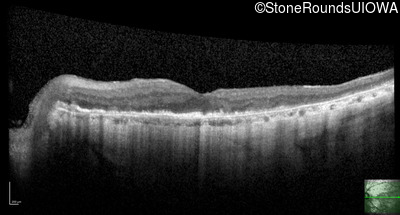

This 81 year old man began using a flashlight to read menus in his 40's. At age 75 his ophthalmologist noticed abnormal fundus findings and referred him to a retina specialist.